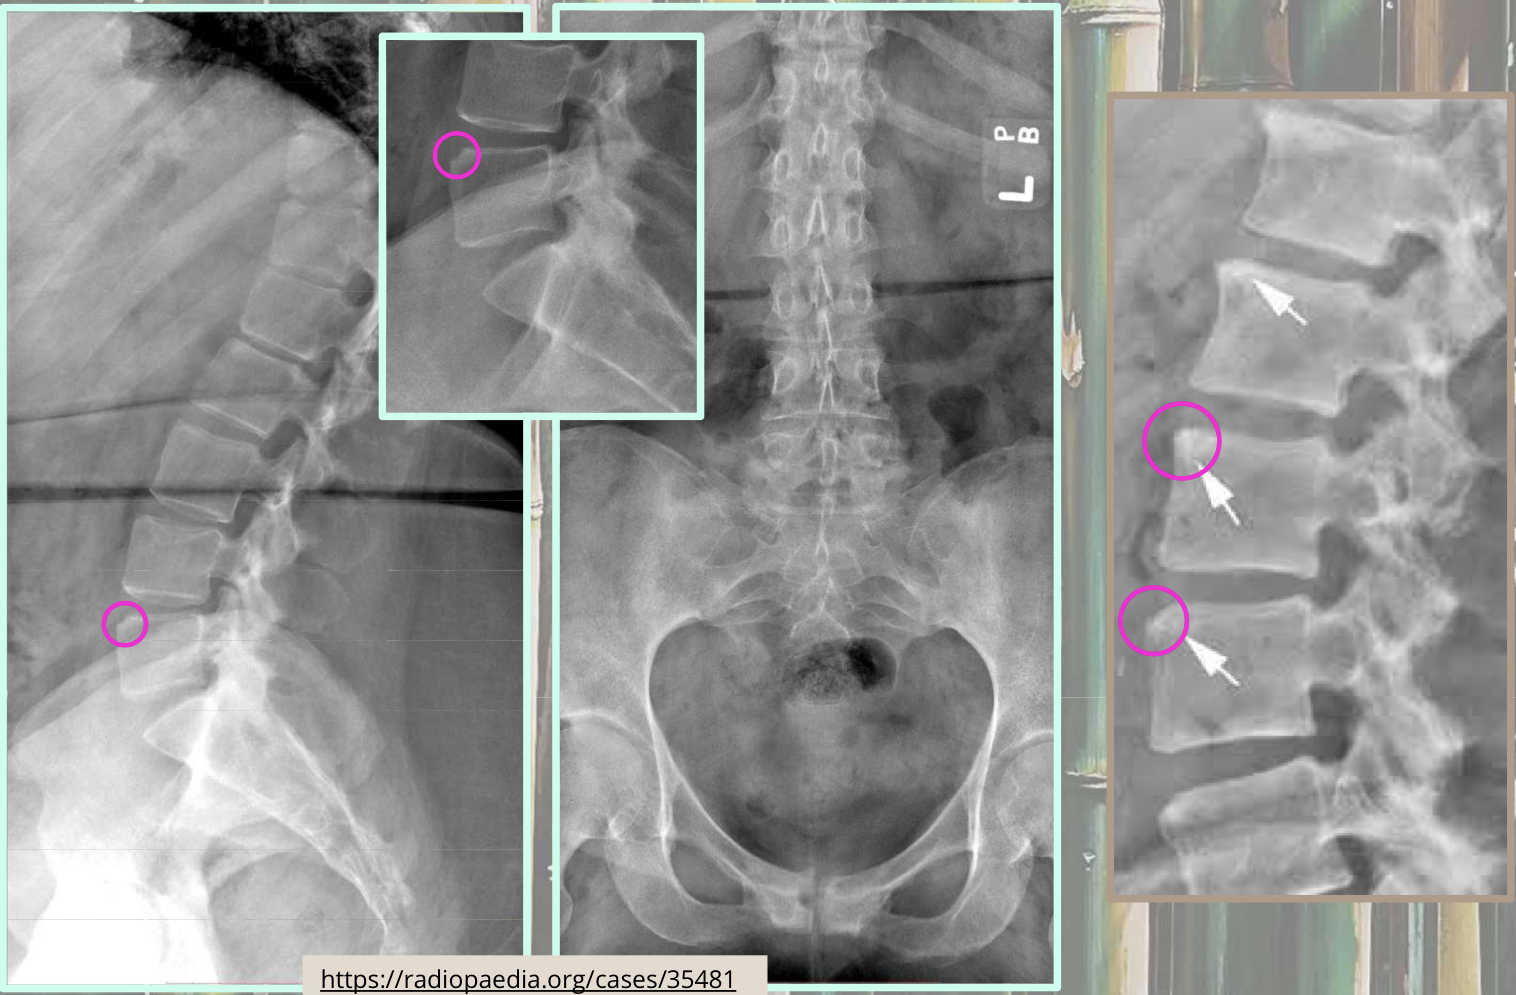

What two findings of AS are found in this image

Corner erosions (Romanus lesions)

Reactive sclerosis (shiny corner)

Loss of anterior concavity (vertebrae squaring)